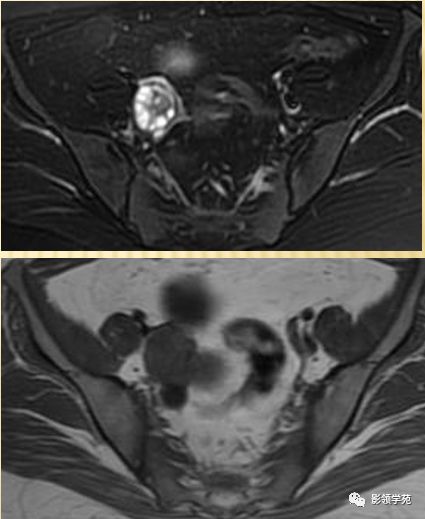

DWI:局限性高信号,癌组织ADC值<癌旁组织<小于正常宫颈组织

DWI显示淋巴结肿大

磁共振动态增强在宫颈癌中的应用